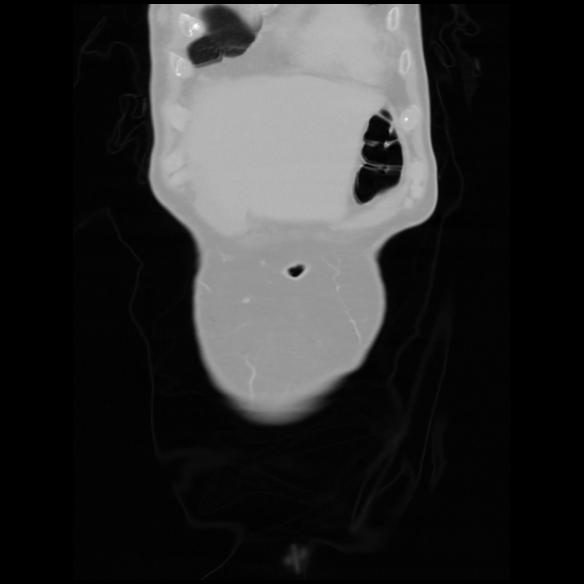

6 CUERPO,CE,Coronal,3.000,CUERPO,Coronal,